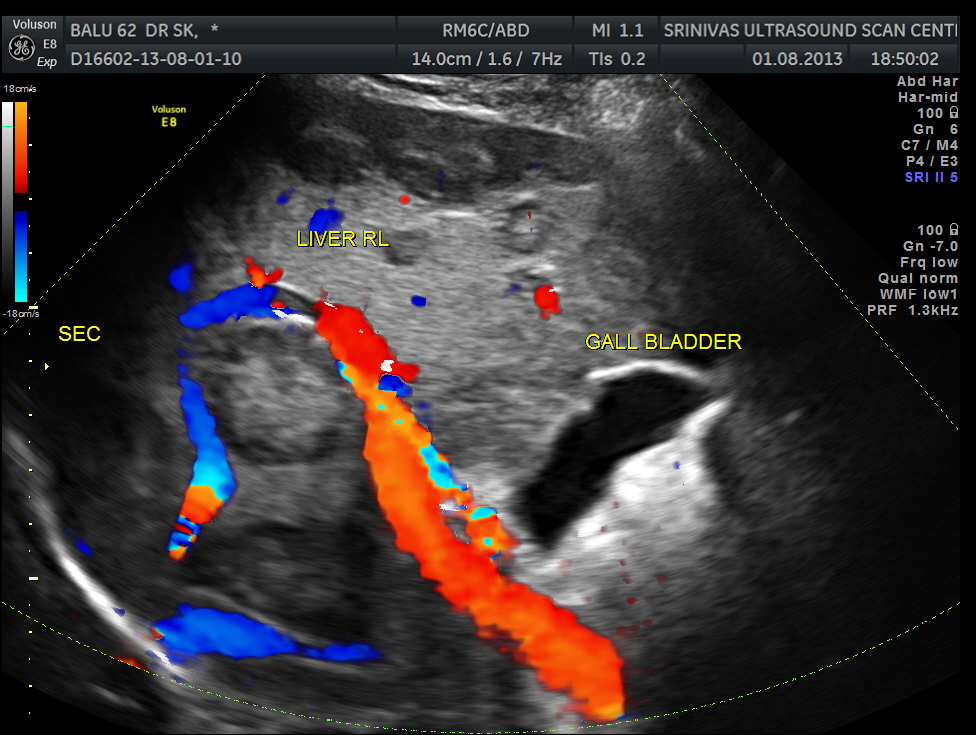

His liver showed multiple secondaries .

The diagnosis offered was multiple liver secondaries with incidental finding of shrunk right kidney with probable reduced function.